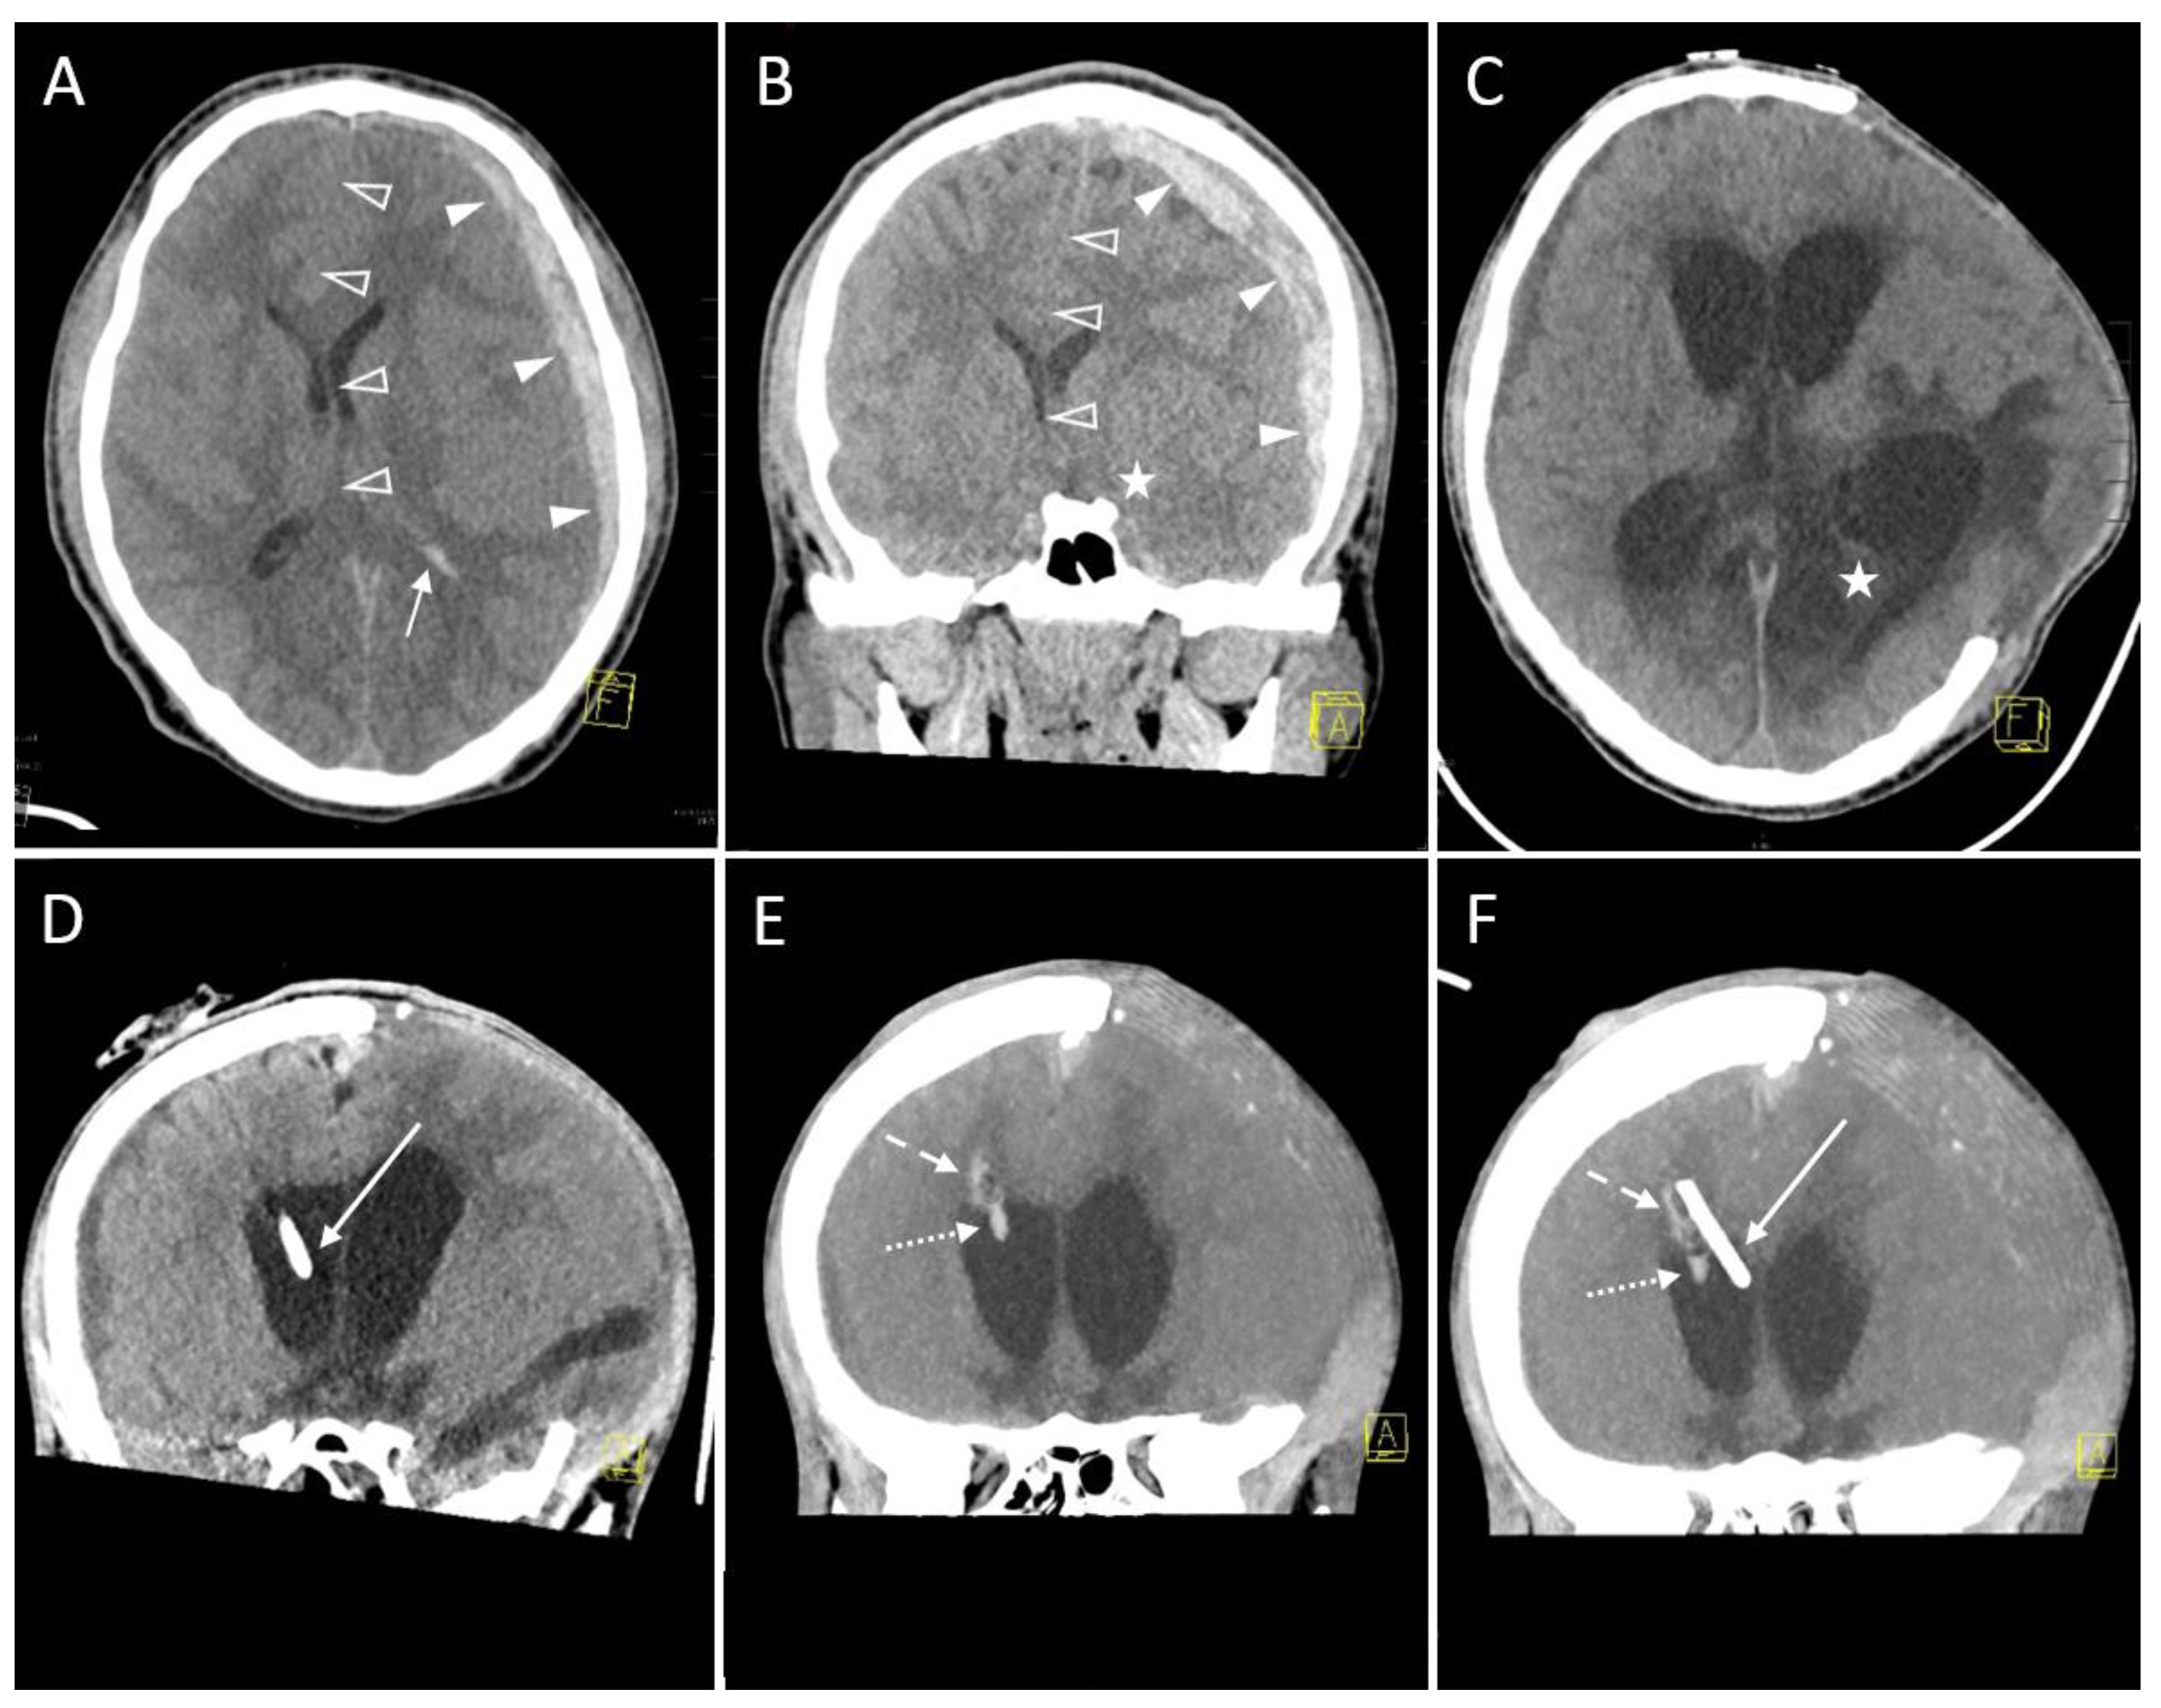

However, in 11 (30.6%) sessions the neurosurgeon decided to proceed with applying either further EVD insertion (n = 5, 13.9%) or withdrawal (n = 1, 2.8%) or modification (n = 5, 13.9%) of the EVD position in case of inadvertent touching or penetration of critical structures or impossible aspiration (head (n = 1) or body (n = 1) of caudate nucleus, internal capsule (n = 1), knee of corpus callosum (n = 1, Figure 3) and septum pellucidum towards contralateral ventricle (n = 1).

Figure 3.

A 14-year-old female with a subarachnoid hemorrhage (Fisher Grade IV) after a motor vehicle accident. (A) Planning a CT scan revealed blood collections in the pentagonal and perimesencephalic cisterns (arrowheads). Yellow graphic: orientation cube (f: frontal). (B) The Evans index of 0.29 (ratio of the maximum width of the frontal horns of the lateral ventricles (37 mm, solid line) and the maximal internal diameter of the skull (129 mm, dashed line)) was in borderline range, suspicious for slightly increased ventricular width. Consequently, the indication for EVD placement was given. Yellow graphic: orientation cube (f: frontal). (C) After EVD placement aspiration of cerebrospinal fluid was not possible. Sagittal reconstruction of the first control scan showed a malposition of the drainage tip in the anterior body of the corpus callosum (dashed arrow). Yellow graphic: orientation cube. (D) Sagittal Maximum Intensity Projection (MIP; 6 mm slice thickness) of the control scan after repositioning of the EVD. The drainage tip is now correctly placed in the anterior horn of the lateral ventricle (solid arrow). (E) A control MRI scan 2 years later shows the puncture channels of the EVD malposition (dashed arrow) as well as their correction placement (solid arrow) as parenchymal defects.

Only in two (5.6%) sessions four control CT scans were required to ensure a functioning final EVD position, one of them remaining a Kakarla II EVD position within the frontal horn of the contralateral ventricle.